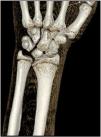

The wrist radiograph (Fig. 1) showed what seemed like a deviation of the distal epiphysis of the radius and a V-shaped carpus, with no differences between the two wrists. A watchful waiting approach was taken, with provision of conservative treatment with an elastic brace and analgesics and follow-up in the outpatient trauma clinic once Madelung deformity was confirmed with a CT scan (Fig. 2).

Madelung deformity is a rare congenital anomaly of the wrist involving a radial deformity with inclination of the radial physis toward the ulnar physis due to an abnormal Vikers ligament or asymmetric growth at the physis. It is more frequent in de girls with bilateral involvement and onset between ages 8 and 12 years.1 The diagnosis is made by means of plain radiography, which allows visualization of an increased distal radius volar tilt, subluxation of the ulnar head and a V-shaped carpus,2 although computed tomography or magnetic resonance imaging can be used to obtain higher-resolution images. The treatment depends on the level of pain and functional impairment, and conservative treatment with wrist splinting is usually sufficient.1